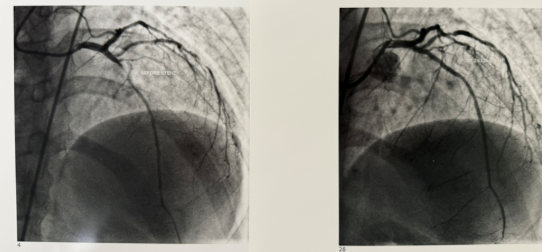

Percutaneous Coronary Intervention (PCI)

Stent placement after balloon angioplasty widens a narrowed coronary artery.

A coronary stent helps keep the artery open and restore healthy blood flow